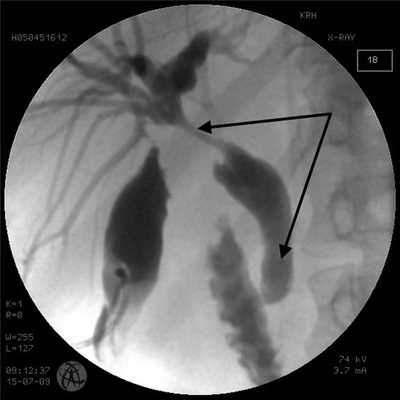

Рис. 1. Антеградная холангиограмма пациента с опухолью Клацкина тип I по Bismuth. Супрапапиллярное расположение наружновнутреннего дренажа (стрелки).